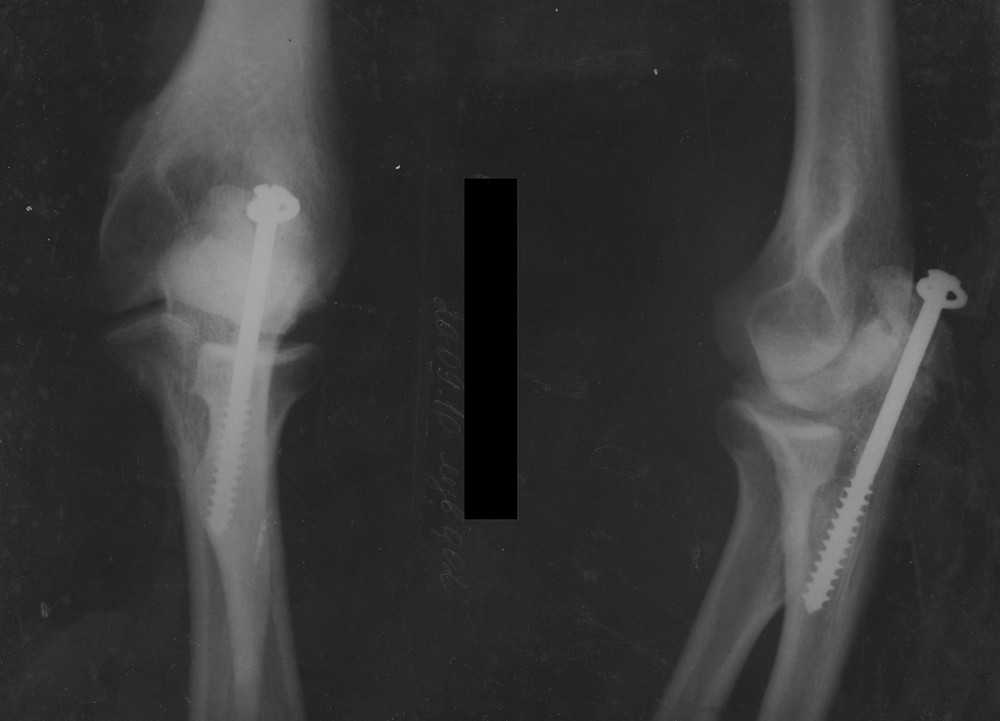

[Ortho] Ложный сустав локтевого отростка

Обещанные снимки.